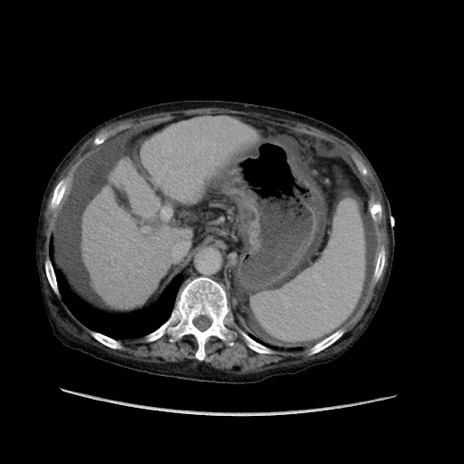

症例31(横断像)

【症例】80歳代 女性

【主訴】腹部膨満感

【現病歴】他院にて肝硬変にてフォロー中。1週間前から便秘、腹部膨満感、臍部腫瘤あり受診となる。

【既往歴】肝硬変

【身体所見】腹部膨隆あり、皮膚変化なし、疼痛なし。

【データ】WBC 4600、CRP 0.25